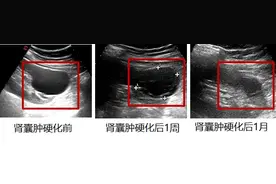

首先,体检发现肾囊肿不需要惊慌,99%的肾囊肿就是肾脏长了一个水泡,大家可以看看下面这张图片:肾囊肿是成年人肾脏最常见的一种结构异常,可以为单侧或双侧,一个或多个,直径一般2cm左右,也有直径达10cm的囊肿,大小不一。